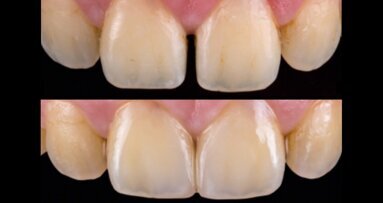

La confección de microcarillas no invasivas mediante sistemas CAD/CAM planteaba hasta ahora un difícil reto debido a la fragilidad de los materiales ...

El Dr. Andreas Kurbad, experto alemán en Odontología Estética, explica en el siguiente caso clínico que las correcciones estéticas con carillas deben ...